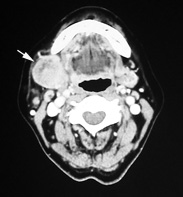

「顎下リンパ節腫瘤の1例」木下 真奈1, 星 昭二2(1浜松医大病理部, 2静岡済生会総合病院)231SPS-case03 [2010]

60歳代女性

1ヶ月前より疼痛を伴う右側頸部腫脹が突然生じ近医を受診。顎下三角部を中心に側頸部全体が強く腫脹していた。抗生剤とステロイド投与によりやや軽快したが3個の腫瘤が残存した。うち一個は以前から存在していたが残り2個は2ヶ月ほど前に初めて自覚している。当院を紹介受診となり側頸部腫瘤生検の結果悪性リンパ腫が疑われ血液内科に入院治療となった。